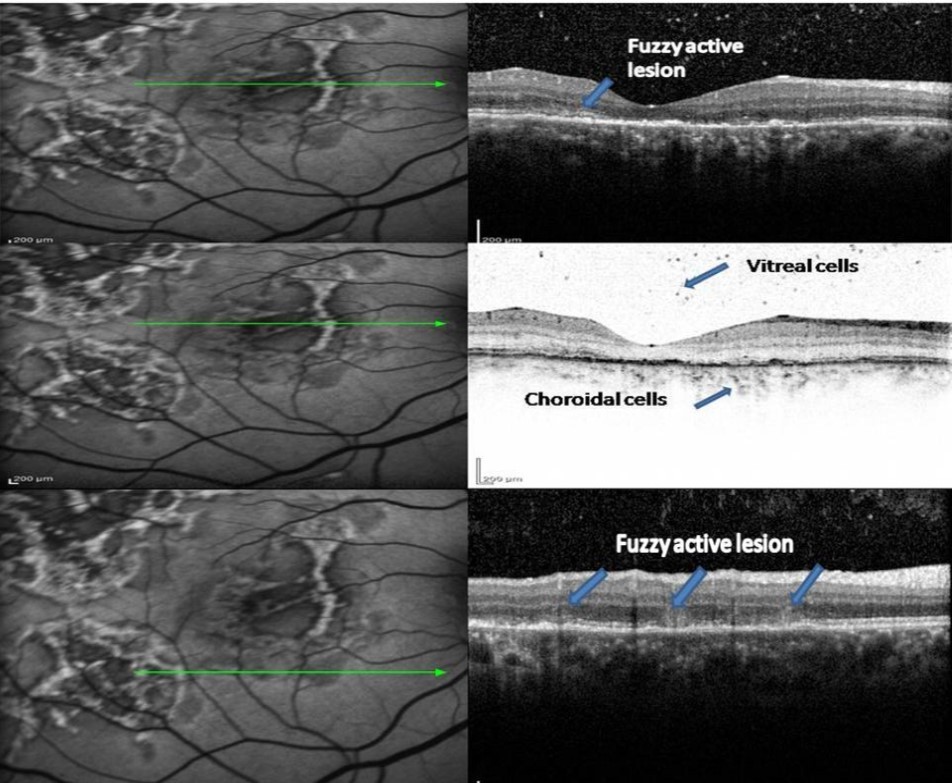

1. In an acute lesion of MCS, there was an ill-defined area of increased autofluorescence around the lesion. The SD-OCT passing through the area showed a localized, fuzzy area of hyperreflectivity in the outer retinal layers involving the RPE, photoreceptor outer segment tips (POST), photoreceptor inner segment–outer segment (IS/OS) junction, external limiting membrane (ELM), and the outer nuclear layer (ONL). The lesion was localized external to the outer plexiform layer with a mild distortion of the inner retinal layers. Choroidal and intra retinal layer cells infiltrate with corresponding increase thickness of choroid and inner retinal layers more obvious in EDI-OCT. There was no increased backscattering from the inner choroid.

A 34-year-old male presented with decreased vision in Right eye since one and half month. On examination, the BCVA was 6/ 60 and 6/6 in the right and left eyes, respectively. Both eyes showed unremarkable anterior segment and multifocal lesions of active as well as inactive choroiditis in the posterior pole of Right eye and healed choroditis on left eye (Figure 1). Simultaneous FAF and SD-OCT imaging of the right eye revealed findings as explained in the “Results” Section (1.) (Figure 2). The tuberculin skin test was positive. He received four-drug antitubercular therapy with oral corticosteroids. About 2 weeks later, the lesions started to heal and appeared as described in “Results” Section (2.) (Figure 3). Three months later, the lesions healed further and appeared as explained in “Results” Section (3.) (Figure 4). Figure 5, Figure 6.

Figure 2.FAF (left) and corresponding eye-tracked SD-OCT image (right) of patient 1 an acute stage of the right eye shows fuzzy area of hyperreflectivity in the outer retinal layers involving the RPE, photoreceptor outer segment tips (POST), photoreceptor inner segment–outer segment (IS/OS) junction, external limiting membrane (ELM), and the outer nuclear layer (ONL) with vitreal and choroidal cells